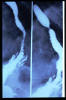

Hernia de hiato por deslizamiento al TGED.

Hernia de hiato por deslizamiento al TEGD.